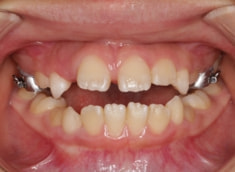

治療前

治療開始時